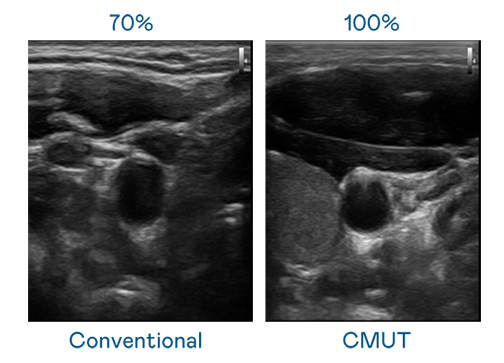

CMUT 技术是一种用电容式微机电元件来产生超音波讯号的技术。与传统 PZT 压电式技术相比,CMUT 频宽增加 30%,更宽频的超音波讯号让影像解析度大幅提升,是实现高影像品质医疗超音波扫描、促进精准医疗发展的关键技术。

大频宽带来超清晰影像

超音波影像的解析度高低,首先取决于探头能发出的讯号频宽。j9九游会(中国)官方网站 CMUT 可提供高清晰的超音波讯号,提供高频宽、高灵敏度、影像纹理细节更高的超音波影像,协助医护人员缩短影像判读时间及利用精准的医疗影像进行诊断。